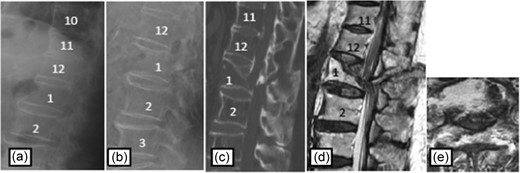

Case 3

Plain radiographs on initial assessment (a) and on admission (b); Sagittal CT image (c) showing the hyperextension fracture at L1 and dislocation of it; MRI T2-weighted image (d, e) showing the severely compressed spinal cord at T12 level.